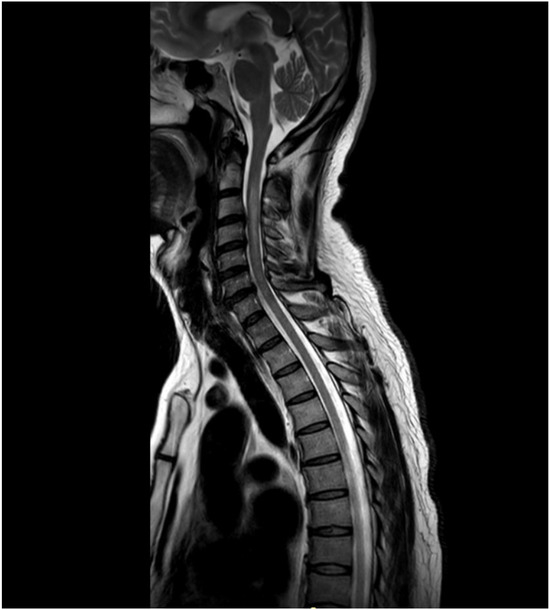

Background: Neuromyelitis optica spectrum disorder (NMOSD) is an autoimmune demyelinating disease with important disability accumulation. Early-onset NMOSD, defined as disease onset before age 50, exhibits distinct clinical characteristics compared to late-onset disease. We present a case series of patients with first symptom onset

Background: Neuromyelitis optica spectrum disorder (NMOSD) is an autoimmune demyelinating disease with important disability accumulation. Early-onset NMOSD, defined as disease onset before age 50, exhibits distinct clinical characteristics compared to late-onset disease. We present a case series of patients with first symptom onset before age 30. Methods: A retrospective review of 10 patients diagnosed with NMOSD at our center in San Luis Potosí, Mexico, with disease onset before age 30. Clinical presentation, imaging findings, AQP4 antibody status, treatment response, and disability outcomes were analyzed. Results: The mean age at onset was 18.6 years (range 6–30). Area postrema syndrome was the most common presentation (40%), followed by acute myelitis and optic neuritis (30% each). All tested patients were AQP4-positive. The mean EDSS at follow-up was 6.6, indicating severe disability. Most patients received rituximab with variable response rates. Conclusions: Our cohort showed higher disability than reported in other early-onset series, emphasizing the need for prompt diagnosis and aggressive treatment in this population.

Figure 1